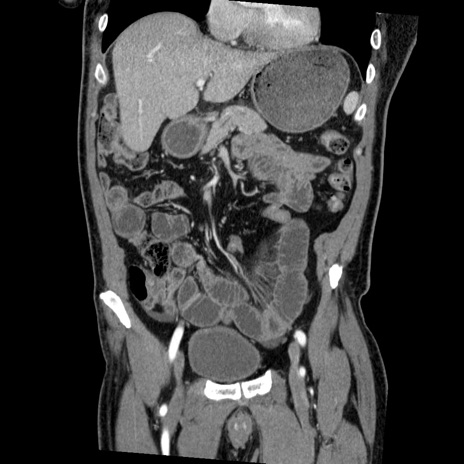

症例22(冠状断像)

【症例】50歳代男性

【主訴】腹痛

【現病歴】AVMからの被殻出血のため回復期リハ病棟入院中。 本日午後3時頃急に下腹部痛が出現した。

【既往歴】AVM、被殻出血、虫垂炎、高血圧

【身体所見】意識晴明、左半身不全麻痺、会話の理解は良好、36.5°C、腹部:膨隆、全体に板状硬、下腹部正中に圧痛点あり、反跳痛-、筋性防御不明、右下腹部にope scar

【データ】WBC 9400、CRP 0.06